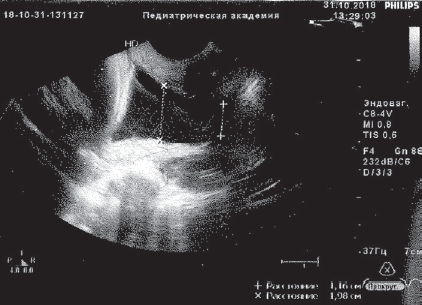

Пациентка М., 35 лет. В анамнезе: хронический тонзиллит, варикозная болезнь нижних конечностей, 1 срочные роды, два года назад — лазерная эксцизия шейки матки по поводу эрозированного эктропиона. Вторая беременность: в сроке 7 недель проводилось стационарное лечение при угрозе прерывания с формированием ретрохориальной гематомы на фоне кольпита. Неоднократно, несмотря на лечение, в динамике из выделений цервикального канала высевалась кишечная палочка. В дальнейшем трижды госпитализировалась по поводу угрозы прерывания (получала магнезию, утрожестан, амоксиклав и др.), В сроке 19 недель выявлена ИЦН, введен АРП. Поступила в ПЦ СПбГПМУ при беременности 25 недель и 3 дня по поводу угрожающих очень ранних преждевременных родов на фоне ИЦН (длина шейки матки по данным УЗИ — 6,9 мм, цервикальный канал на всем протяжении расширен до 11 м). В посеве из влагалища выделена кишечная палочка, в анализе крови данные за умеренную гиперкоагуляцию, СОЭ 44 мм/ч, ЛИИ — 3,2 усл. ед. Получала комплексную медикаментозную терапию (трактоцил, профилактику РДС, клексан и др.), три сеанса малообъемного МПА в сочетании с лазерным (№ 5), ультрафиолетовым (№ 6) облучением крови. Ослож нений не было. При контрольном УЗИ отмечено формирование незначительной сохранной части шейки матки, которая составила 7,3 мм (рис. 4, 5).

Рис. 4. Данные ультразвукового исследования пациентки М. до курса эфферентной терапии

Fig. 4. Ultrasonic examination of patient M. before efferent therapy

Рис. 5. Данные ультразвукового исследования пациентки М. после курса эфферентной терапии — положительная динамика

Fig. 5. Ultrasonic examination of patient M. after efferent therapy course — positive results